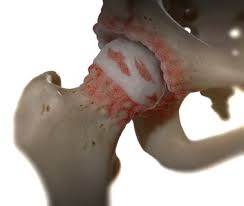

고관절 통증이 나타나는 위치

고관절 통증은 엉덩이 깊숙한 부위에서만 느껴진다고 생각하기 쉽지만, 실제로는 다양한 위치로 퍼져 나타날 수 있습니다.

• 사타구니 안쪽 통증

• 엉덩이 한쪽 깊은 통증

• 허벅지 앞쪽 또는 옆쪽 통증

• 무릎까지 이어지는 불편감

특히 사타구니 통증은 고관절 이상을 가장 강하게 의심할 수 있는 신호로 전문가들도 중요하게 보는 증상입니다.